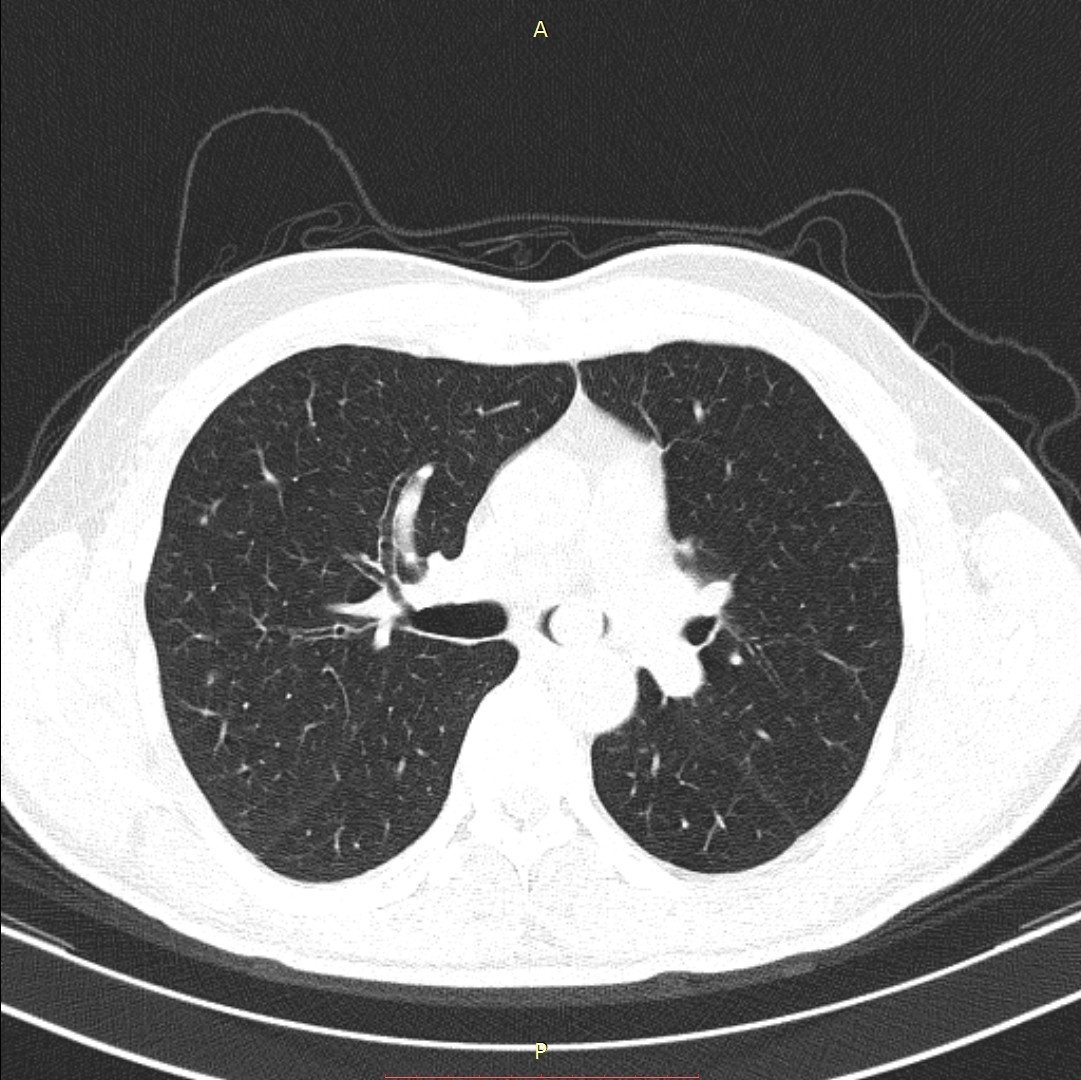

- გულმკერდის კტ (Axial) რეზექციამდე 2 კვირით ადრე

სიმსივნური წარმონაქმნი მარცხენა მთავარ ბრონქში.

აღინიშნება მარცხენა ფილტვის თითქმის სრული ატელექტაზი.